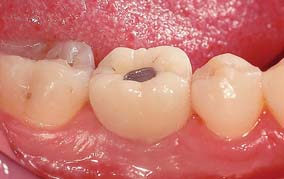

Several systems have been developed to comply with these demands. Common indications include congenitally missing maxillary lateral incisors (Fig. 13-42) and teeth in which endodontic treatment was unsuccessful (Fig. 13-43). Screw loosening has most commonly been associated with the terminally positioned single molar implant crown (Fig. 13-44).

Fig. 13-43 A, Occlusal view of a single tooth implant crown replacing a fractured mandibular premolar. B, Implant crown with screw access restored.